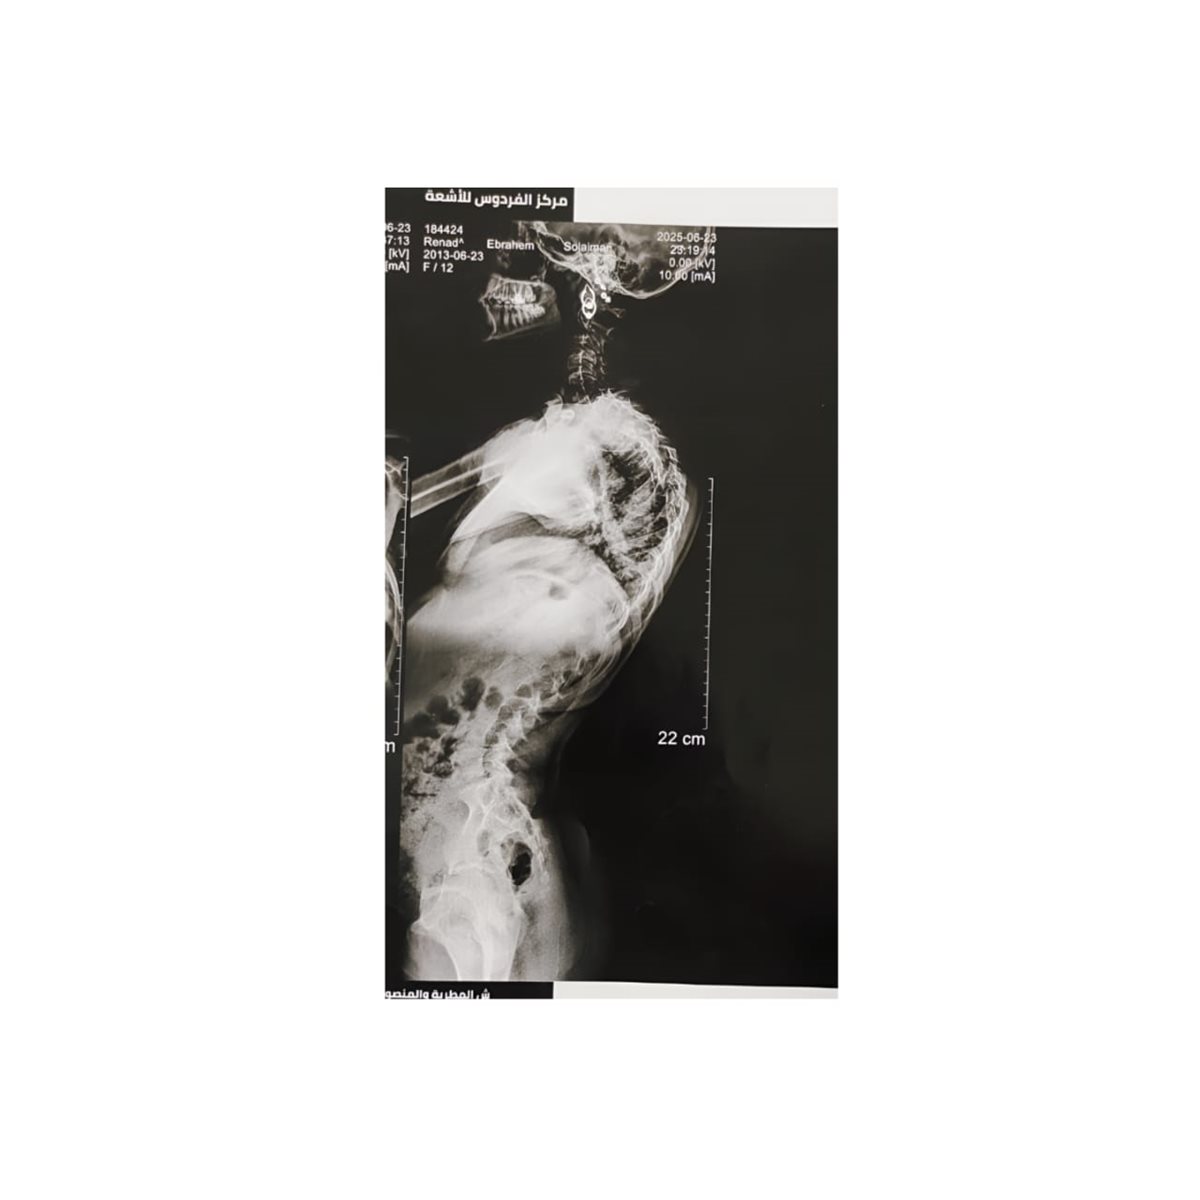

وقال: ان الحالة حضرت للمستشفى وهي تعاني من اعوجاج شديد وتحدب واضح بالعمود الفقري (حالة تشوه فقري معقد) أثّر على اتزان العمود الفقري ووظائفه الحيوية، مما استدعى التدخل الجراحي الدقيق لإعادة الاستقامة والتوازن الفقري عبر عملية إصلاح وتثبيت داخلي.